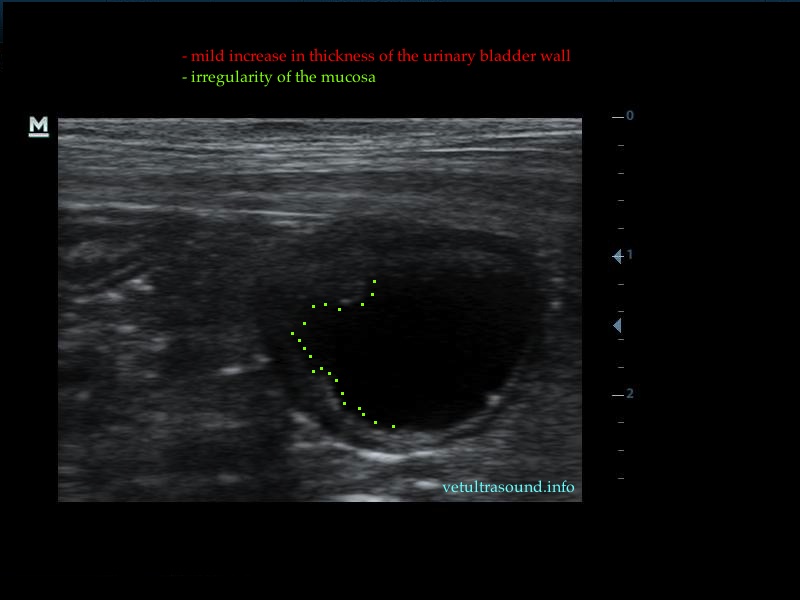

In all the following cases, urinary samples were taken for culture, in order to confirm the diagnosis of bacterial cystitis. In most cases the urinary bladder was almost empty due to polyuria, so we had to wait for about fifteen minutes, with or without the use of furosemide.

The increase of thickness of the urinary bladder wall and the striation of the mucosa is evident. Inguinal lymphnodes are usually prominent and mildly enlarged. Colour Doppler may reveal the blood flow of the mucosa of the empty urinary bladder, whereas the blood flow in a full bladder appears decreased. This could be because of the fibrosis of the urinary bladder wall and could explain why sometimes chronic conditions like these do not respond well to antibiotics. This pathophysiology has been studied in humans with the use of endoscopic ultrasound.